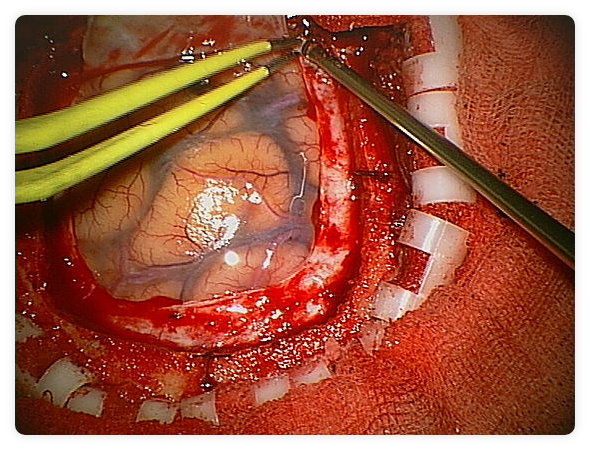

Imagen intraoperatoria durante la extirpación de un tumor cerebral

La craneotomía es una operación quirúrgica que consiste en extraer un colgajo de hueso para acceder al cerebro. Este tipo de intervenciones las realizan exclusivamente los neurocirujanos, en situaciones de emergencia (evacuación de hematomas, contusiones cerebrales…) o bien de forma programada (por ejemplo para la extirpación de un tumor).